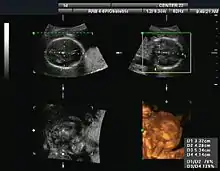

Orthogonal planes of a three-dimensional sonographic volume with transverse and coronal measurements for estimating fetal cranial volume[16][17]

Gynecologic ultrasonography examines female pelvic organs (specifically the uterus, ovaries, and fallopian tubes) as well as the bladder, adnexa, and pouch of Douglas. It uses transducers designed for approaches through the lower abdominal wall, curvilinear and sector, and specialty transducers such as transvaginal ultrasound.[18]

Obstetrical sonography was originally developed in the late 1950s and 1960s by Sir Ian Donald[19][20] and is commonly used during pregnancy to check the development and presentation of the fetus. It can be used to identify many conditions that could be potentially harmful to the mother and/or baby possibly remaining undiagnosed or with delayed diagnosis in the absence of sonography. It is currently believed that the risk of delayed diagnosis is greater than the small risk, if any, associated with undergoing an ultrasound scan. However, its use for non-medical purposes such as fetal "keepsake" videos and photos is discouraged.[21]